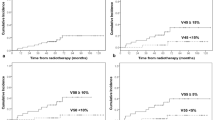

Fisher’s exact test was used to compare proportions between groups. Logistic regression analysis was used to assess the relationship between cardiac complications and covariates of interest, including sex, age, RT technique, mean heart radiation dose, volume of heart irradiated, V30 (percent volume of heart receiving 30 Gy), V40 (percent volume of heart receiving 40 Gy), V50 (percent volume of heart receiving 50 Gy), risk factors for CAD, history of CHF and arrhythmia. Odds ratios and corresponding 95% confidence intervals were estimated from these models. All parameters were tested in univariate analysis, and then factors that were significantly associated with complications were jointly modeled in a multivariate model. Additionally, logistic regression analysis to compare the frequency of risk factors for CAD in esophageal versus lung cancer patients was performed. All statistical tests were two-sided, and P-values of 0.05 or smaller were considered to be statistically significant. Statistical analysis was carried out using the SAS software program version 9 (SAS Institute, Cary, NC).

All patients combined

When the total study population including both esophageal and lung cancer patients were considered in univariate logistic regression analysis, arrhythmia (P = 0.003) and CHF (P = 0.003) were significantly associated with future cardiac complications after CRT. The remaining tested variables did not reach statistical significance as predictors of future cardiac complications in the total study population. When arrhythmia and CHF were included in a multivariate analysis, both CHF (OR = 0.13, 95%CI: (0–1.14), P = 0.065) and arrhythmia (OR: 0.06, 95% CI: (0.02–1.07), P = 0.060) demonstrated marginal statistical significance, as predictors of future cardiac complications.